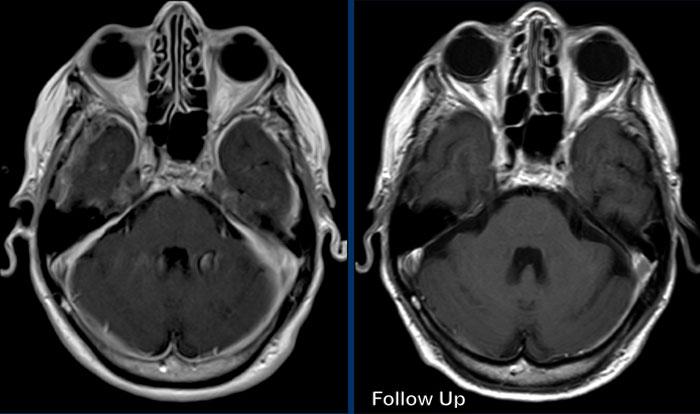

Các hình ảnh này của một bệnh nhân nam 58 tuổi nhập viện với triệu chứng đau đầu ở tư thế ngồi và đứng.

Hình ảnh

Có ngấm thuốc màng cứng đều đặn ở cả khoang trên lều và dưới lều.

Lưu ý các não thất nhỏ.

Hình 2

Sau điều trị bằng miếng vá máu ngoài màng cứng không định vị mục tiêu, não và thân não đã trở về vị trí bình thường với sự bình thường hóa cấu hình các bể và não thất IV.